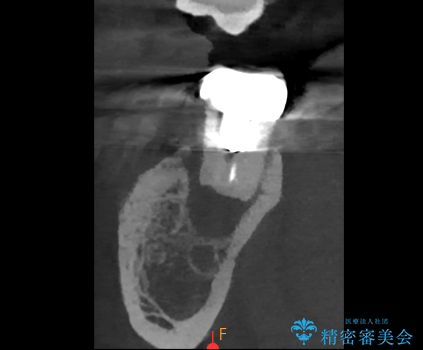

- 過去にヘミセクションが行われていたと思われる左下7番は、大きな歯根嚢胞および根尖病変が認められ、さらに骨縁下カリエスを伴っており、歯肉には瘻孔が形成されている状態でした。

保存は困難と判断し、左下7番は抜歯即時インプラントによる治療を行いました。